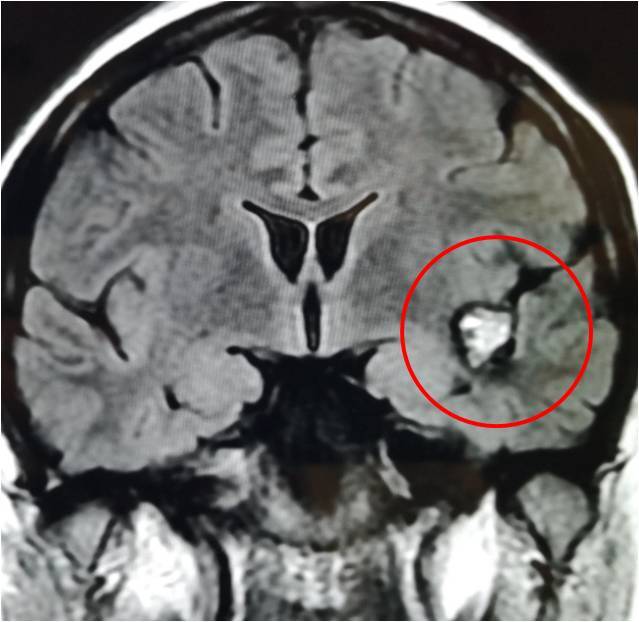

头部磁共振,右侧颞极病变,考虑海绵状血管瘤。

诊断:继发性癫痫,右侧颞叶海绵状血管瘤

综合分析:患者诊断明确,发作形式和脑电图均支持右侧颞区,考虑导致癫痫发作的直接因素为右颞叶的海绵状血管瘤,这种血管瘤的主要临床表现为癫痫发作,可以手术切除,估计术后痊愈的可能性非常大。但术中需要扩大切除血管瘤周边的含铁血黄素,也是导致癫痫发作的主要脑组织。术中可以用皮层脑电检测,定位皮层放电。